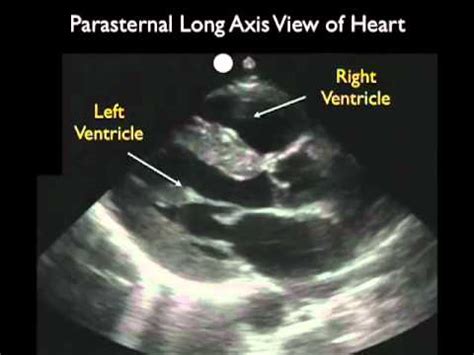

So, you want to master the parasternal long axis view ? This is where the magic happens in echocardiography, folks! This view gives us an incredible look at the left side of the heart. Imagine peering into the heart from the side, seeing the major players lined up perfectly. We’re talking about the left ventricle (LV) , that powerhouse chamber, the mitral valve controlling blood flow into the LV, the aortic valve directing blood out to the body, and the left atrium (LA) receiving blood from the lungs. Getting this view correctly is absolutely essential for assessing LV size and function, detecting mitral regurgitation or stenosis, evaluating the aortic valve, and spotting any enlargement of the left atrium. It’s like getting the money shot of the heart’s pumping action. Without a solid parasternal long axis view, any other echo assessment will be incomplete, possibly even misleading. We’ll guide you through the precise steps to achieve this view, covering everything from where to place the transducer to how to angle it for the best visualization. We’ll also touch on common mistakes and how to fix them, because let’s be real, nobody gets it perfect on the first try, and that’s totally okay! This section is all about building your confidence and competence in one of the most important echocardiographic views.

Let’s chat about why the parasternal long axis view is such a big deal in echocardiography. You might be wondering, “Why this specific view?” Well, guys, it’s all about getting a comprehensive picture of the heart’s most critical components. This view provides a longitudinal or ‘long’ axis view of the left ventricle, allowing us to see its shape, size, and how it’s contracting. We can directly visualize the mitral valve leaflets opening and closing, and assess for any abnormalities like thickening, prolapse, or regurgitation. Similarly, the aortic valve comes into clear view, enabling us to check for stenosis (narrowing) or regurgitation (leakage). The left atrium is also beautifully displayed, so we can measure its size and determine if it’s enlarged, which can be a sign of various heart conditions. Furthermore, the interventricular septum and the posterior wall of the left ventricle are clearly visible, allowing for assessment of wall thickness and motion abnormalities. This view is often the starting point for many echocardiographic examinations because it offers such a wealth of information about the left heart. It’s fundamental for diagnosing conditions such as hypertrophic cardiomyopathy, dilated cardiomyopathy, valvular heart disease, and even helps in evaluating the impact of hypertension on the heart. It’s like having a blueprint of the heart’s main pumping system laid out right in front of you. So, the ‘why’ is simple: it gives us a clear, consistent, and highly informative window into the functional anatomy of the left heart, making it indispensable for accurate diagnosis and management of cardiovascular diseases.